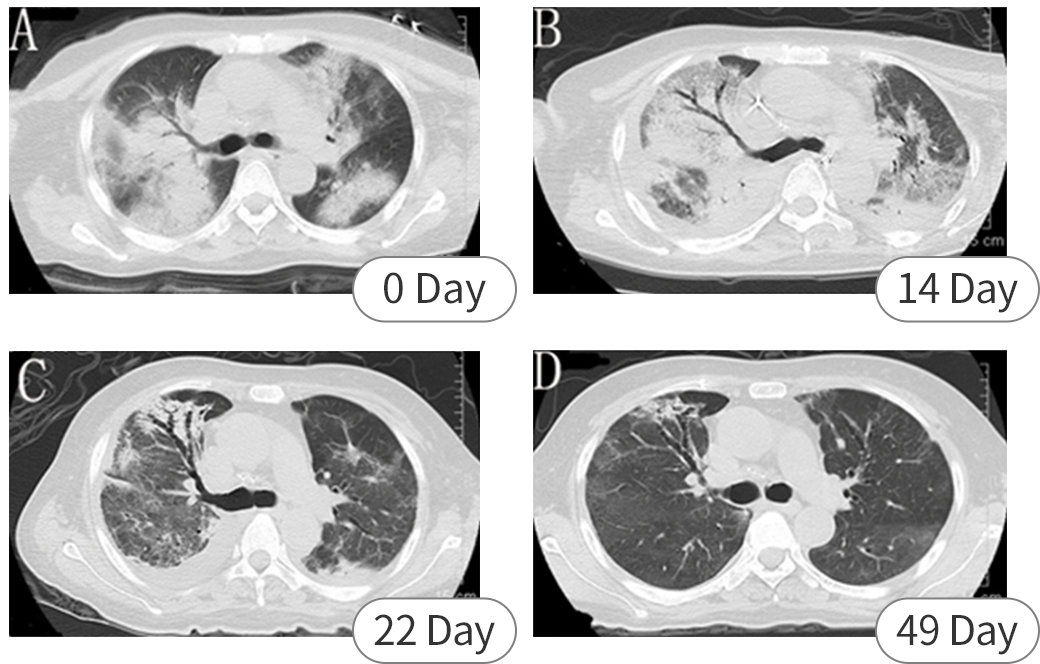

患者女,54岁,反复头痛发热20 d,呼吸困难3 d来院就诊,具体发病及诊疗过程如下:

本案例中,尽管没有明确的鸟类或家禽接触史,两次外周血培养阴性亦为诊断带来了挑战,但通过mNGS 很快在 BALF 和 CSF 中检测到鹦鹉热,支持了临床诊断。